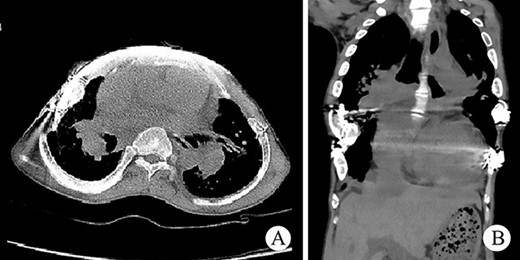

The patient was a 25-year-old man who had respiratory discomfort after birth and was diagnosed as ATD at that time. His respiratory symptoms were obvious in childhood. Hypoxia always appeared when crying but disappeared after rest. After age of 5, his condition gradually stabilized. However, after puberty, his respiratory symptoms reappeared and worsened 1 year before admission. He was admitted to our hospital for surgery finally. Physical examination showed that his thorax was narrow and small (Fig. 1A), and his height was 145 cm and chest circumference was only 63 cm. Imaging examination revealed that there were obvious depressions on both sides of the chest wall (Fig. 1B and C). The operation was carried out under general anesthesia, and performed on both sides of chest wall simultaneously. Two longitudinal incisions were performed on each sides of the chest wall respectively in the axillary midline to expose the ribs and costal cartilages. Two tunnels were made in front of the sternum but beneath the soft tissues of the anterior chest wall, and two arc-shaped steel bars were put into the tunnels, respectively. Both sides of the bars were located in front of the depressions. The structures in the depressions were lifted and fixed on the bars (Fig. 2A–C), and the depressions disappeared completely. After the incisions were closed, the operation was completed (Fig. 1D). The symptoms improved significantly, the blood oxygen saturation maintained over 92%, the chest circumference increased to 70 cm and the appearance of the chest was basically normal postoperatively. The patient was discharged 25 days after operation. Followed up for 1 year, there were no symptoms during daily activities, but there were hypoxia after vigorous activities. Imaging examination showed that the shape of the thorax was significantly improved (Fig. 3A and B).

(A) Thorax appearance before operation; and (B) and (C) CT scan of thorax.